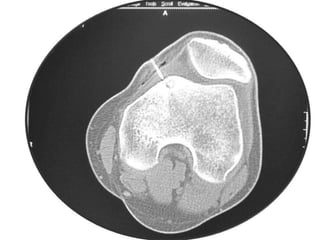

Osteoid Osteoma - CT

• CT is more accurate than MRI.

• CT helped in confirming the diagnosis of

osteoid osteoma in 74% of cases.

• Szendroi et al reported accuracies of about

66% in the diagnosis of intra-articular lesions

and 90% in extra-articular lesions.

• To date, CT scanning is the primary

investigational tool for the definitive diagnosis

of osteoid osteoma.

Osteoid Osteoma -CT • CT is more accurate than MRI. • CT helped in confirming the diagnosis of osteoid osteoma in 74% of cases. • Szendroi et al reported accuracies of about 66% in the diagnosis of intra-articular lesions and 90% in extra-articular lesions. • To date, CT scanning is the primary investigational tool for the definitive diagnosis of osteoid osteoma.